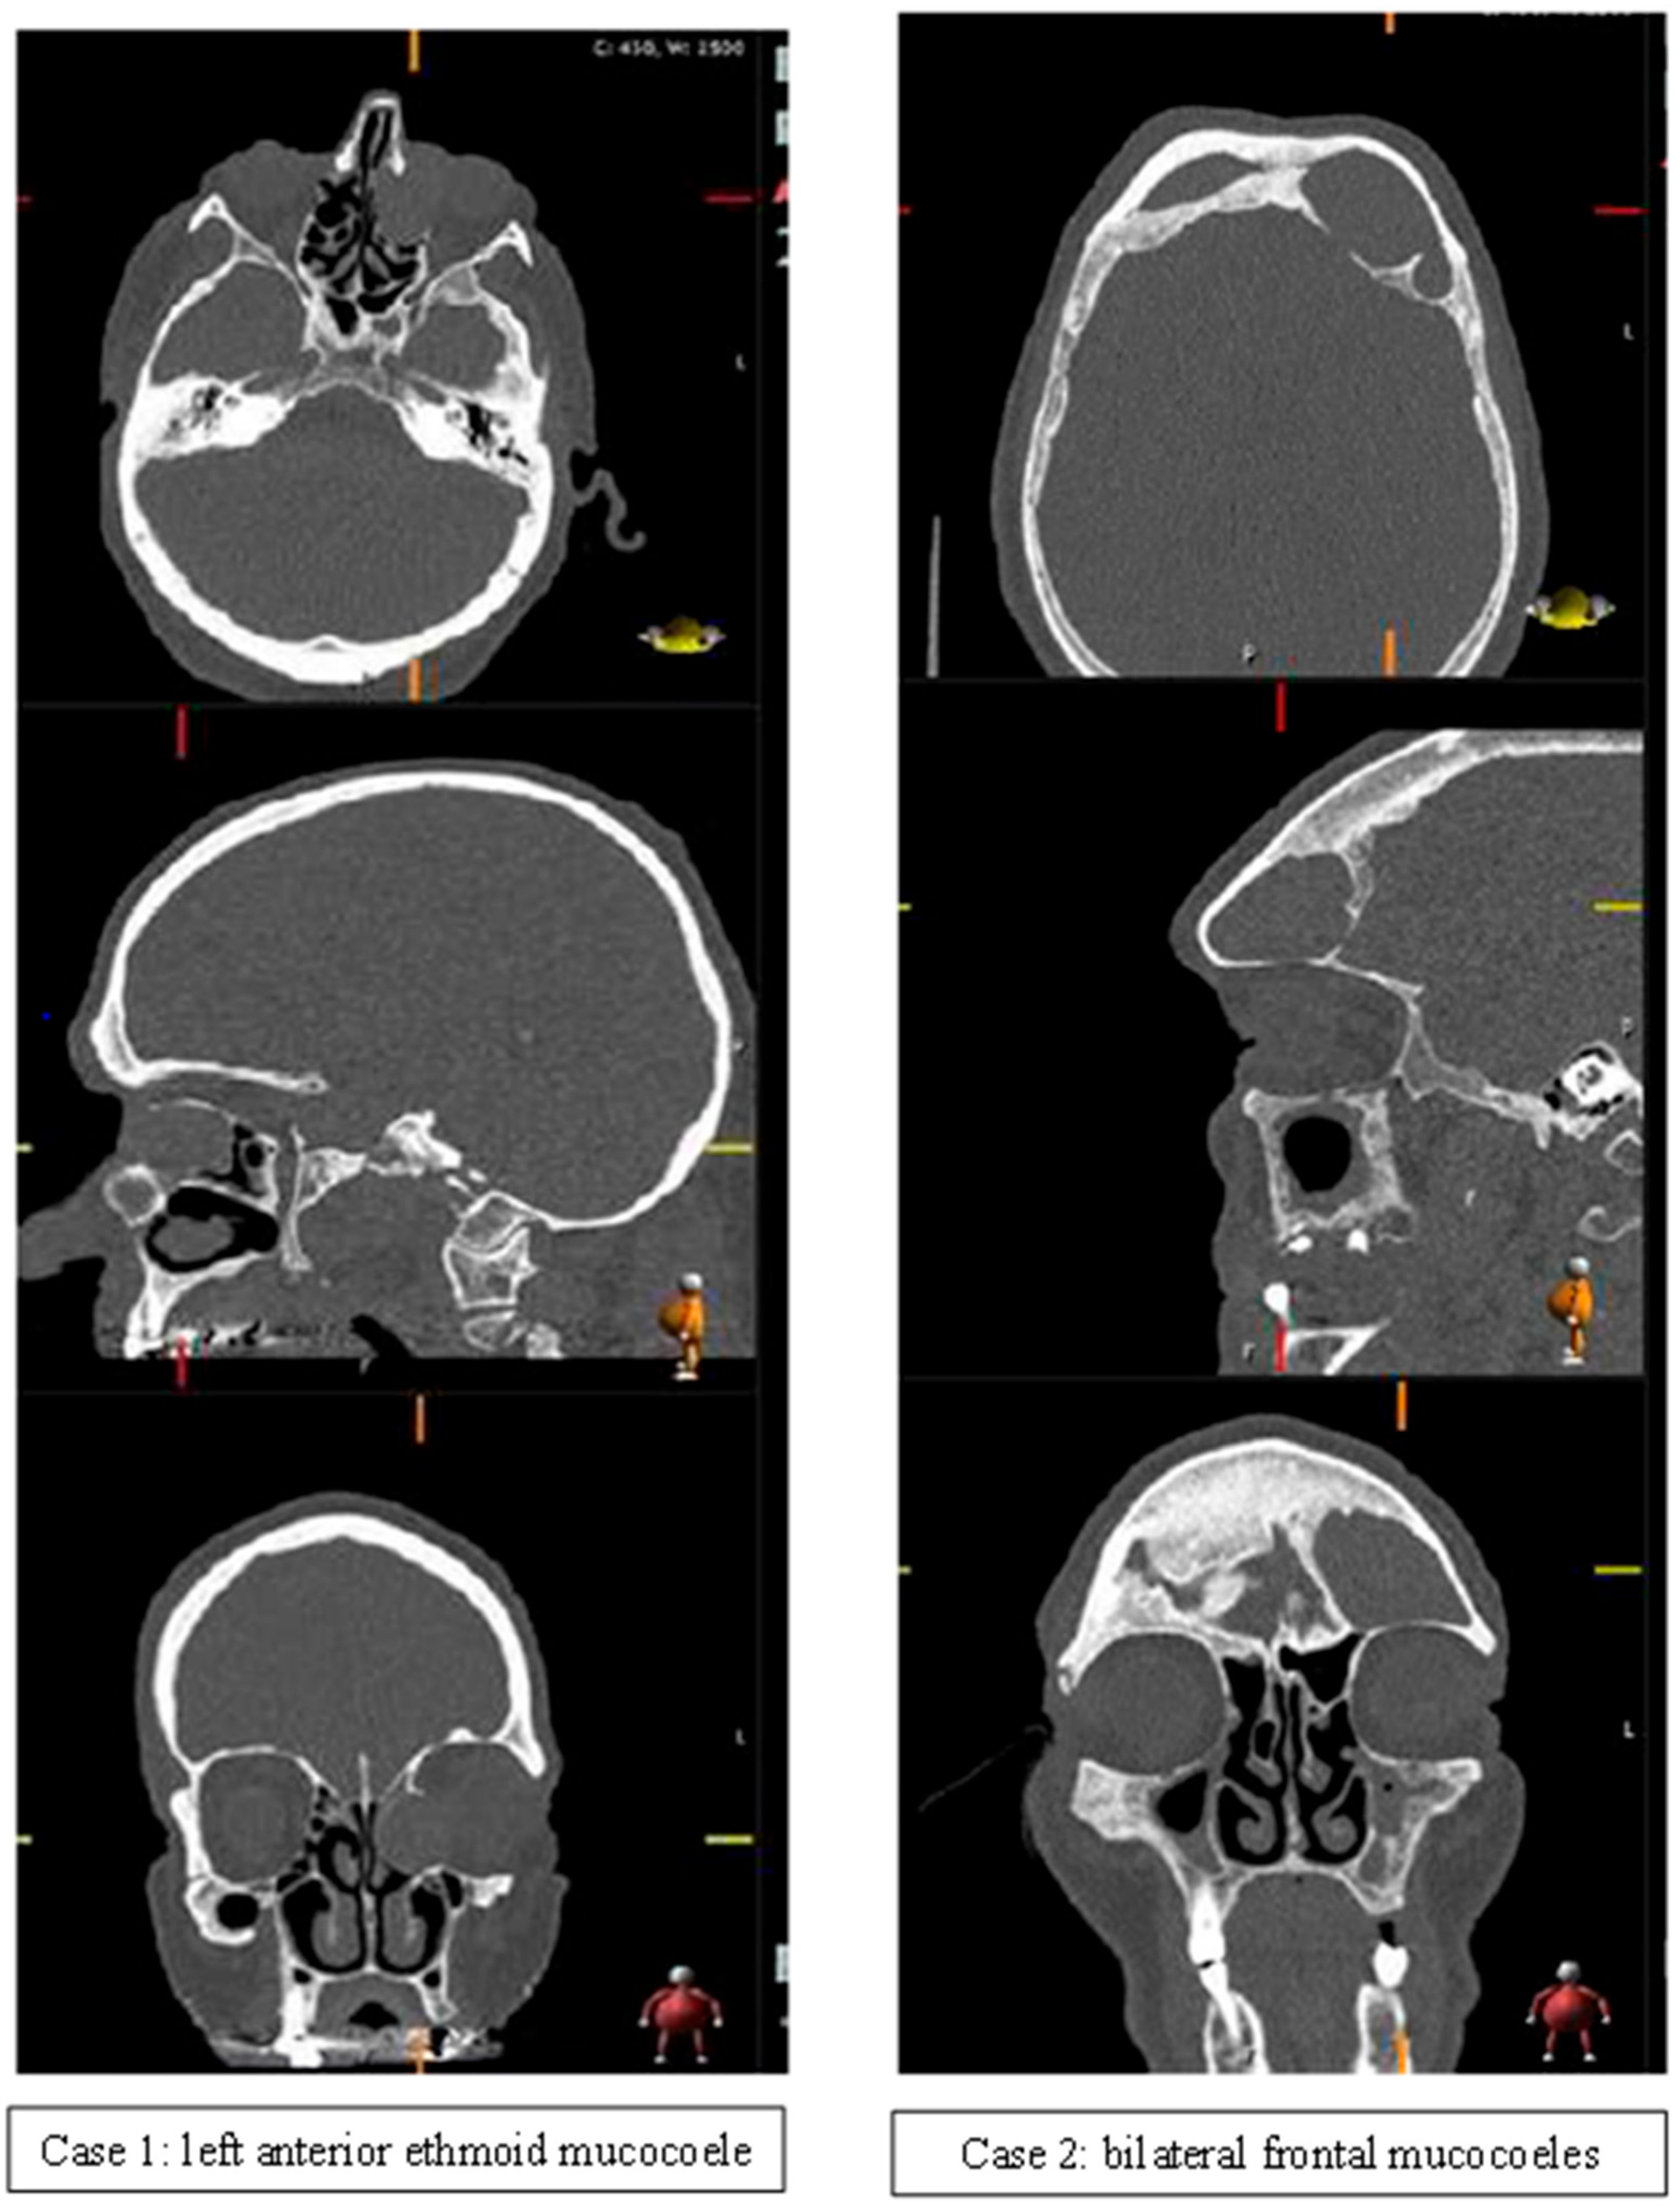

| Ethmoid | 5 (11) | 3 (20) | |